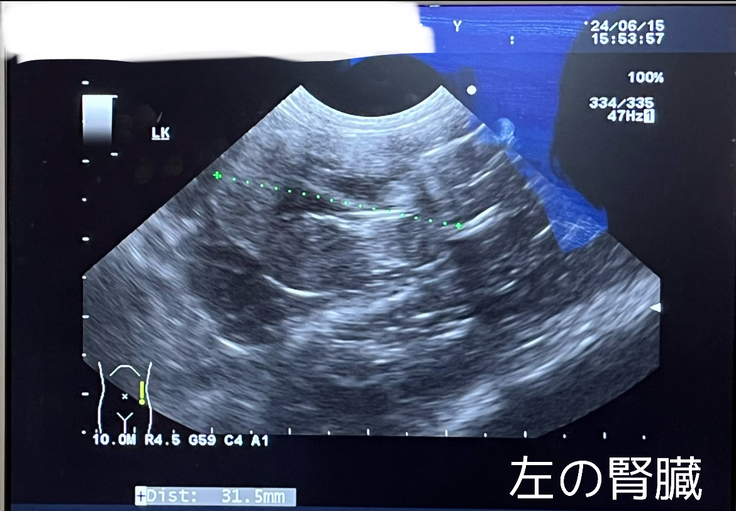

超音波検査ですが、

左の腎臓は変わらず、ボコボコとした腫瘍がたくさんありました。

右の腎臓も変わらず、萎縮しています。